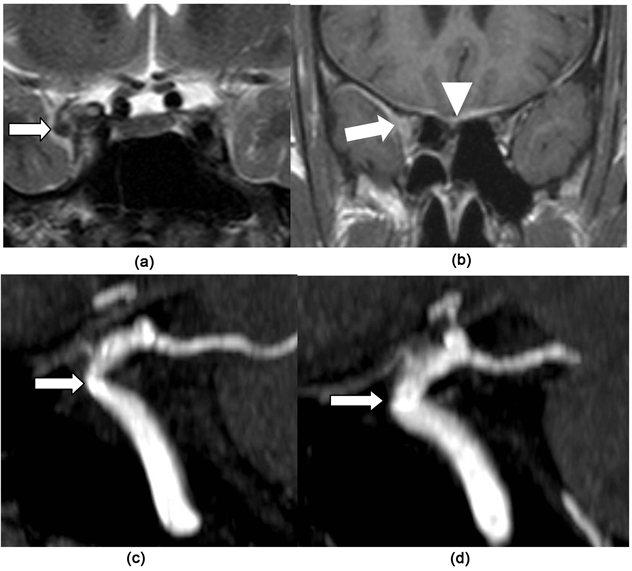

He underwent a MRI examination with the same sequences. It showed an enlargement of the right cavernous sinus compared to the left side. The cavernous sinus appeared isosignal T2 in Figure 2(a). There was a significant gadolinium enhancement after injection. The enhancement extended to the superior orbital fissure and the adjacent pachymeningeal structures as showed in Figure 2(b). The sagittal MIP reconstructions of the TOF sequence showed a slight reduction of the right internal carotid lumen on Figure 2(c) compared to the left side on Figure 2(d). These aspects pleaded, here again for an inflammatory involvement.

Figure 2. The coronal T2 image (a) shows an enlarged isosignal T2 in the right cavernous sinus significantly enhanced after gadolinium injection (arrow (a) and (b)). The image on (b) shows the pachymeningeal contrast enhancement (arrow-head (b)). The sagittal 3D TOF MIP reconstruction (c) shows a slightly decrease lumen diameter of the right internal carotid (arrow (c)) due to inflammation (arteritis) or a slight compression compared to the normal left internal carotid lumen diameter (arrow (d)).

Involvement of the cavernous sinus and the superior orbital fissure in the THS appears as a diffuse infiltration isosignal on T2 weighted sequence with enlargement of the cavernous sinus [Figure 1 and Figure 2] [5] [6] [7] [8] [9] . After gadolinium injection, there is a diffuse and significant enhancement that reaches the neighboring regions such as the orbital apex or the superior orbital fissure. Sometimes it is associated with a contrast enhancement of the adjacent pachymeningeal structures as noted on Figure 2.

Carotid involvement is part of the original description of Tolosa. It seems to be a characteristic [3] [4] [5] [6] that can be related to compression by the granuloma and/or vasculitis substantially reducing the carotid lumen as observed in our patients [Figure 1 and Figure 2]. Carotid involvement seems not to have any major encephalic consequence such as ischemia throughout literature. So there was in our patients.